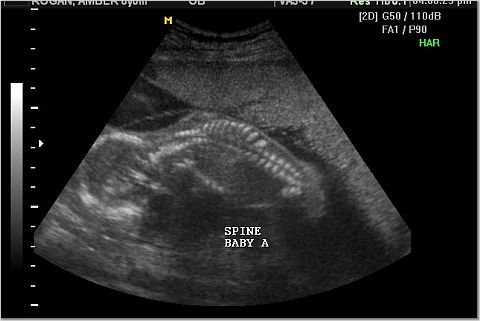

Pictures from Ultrasona

Baby A and Baby B Spine